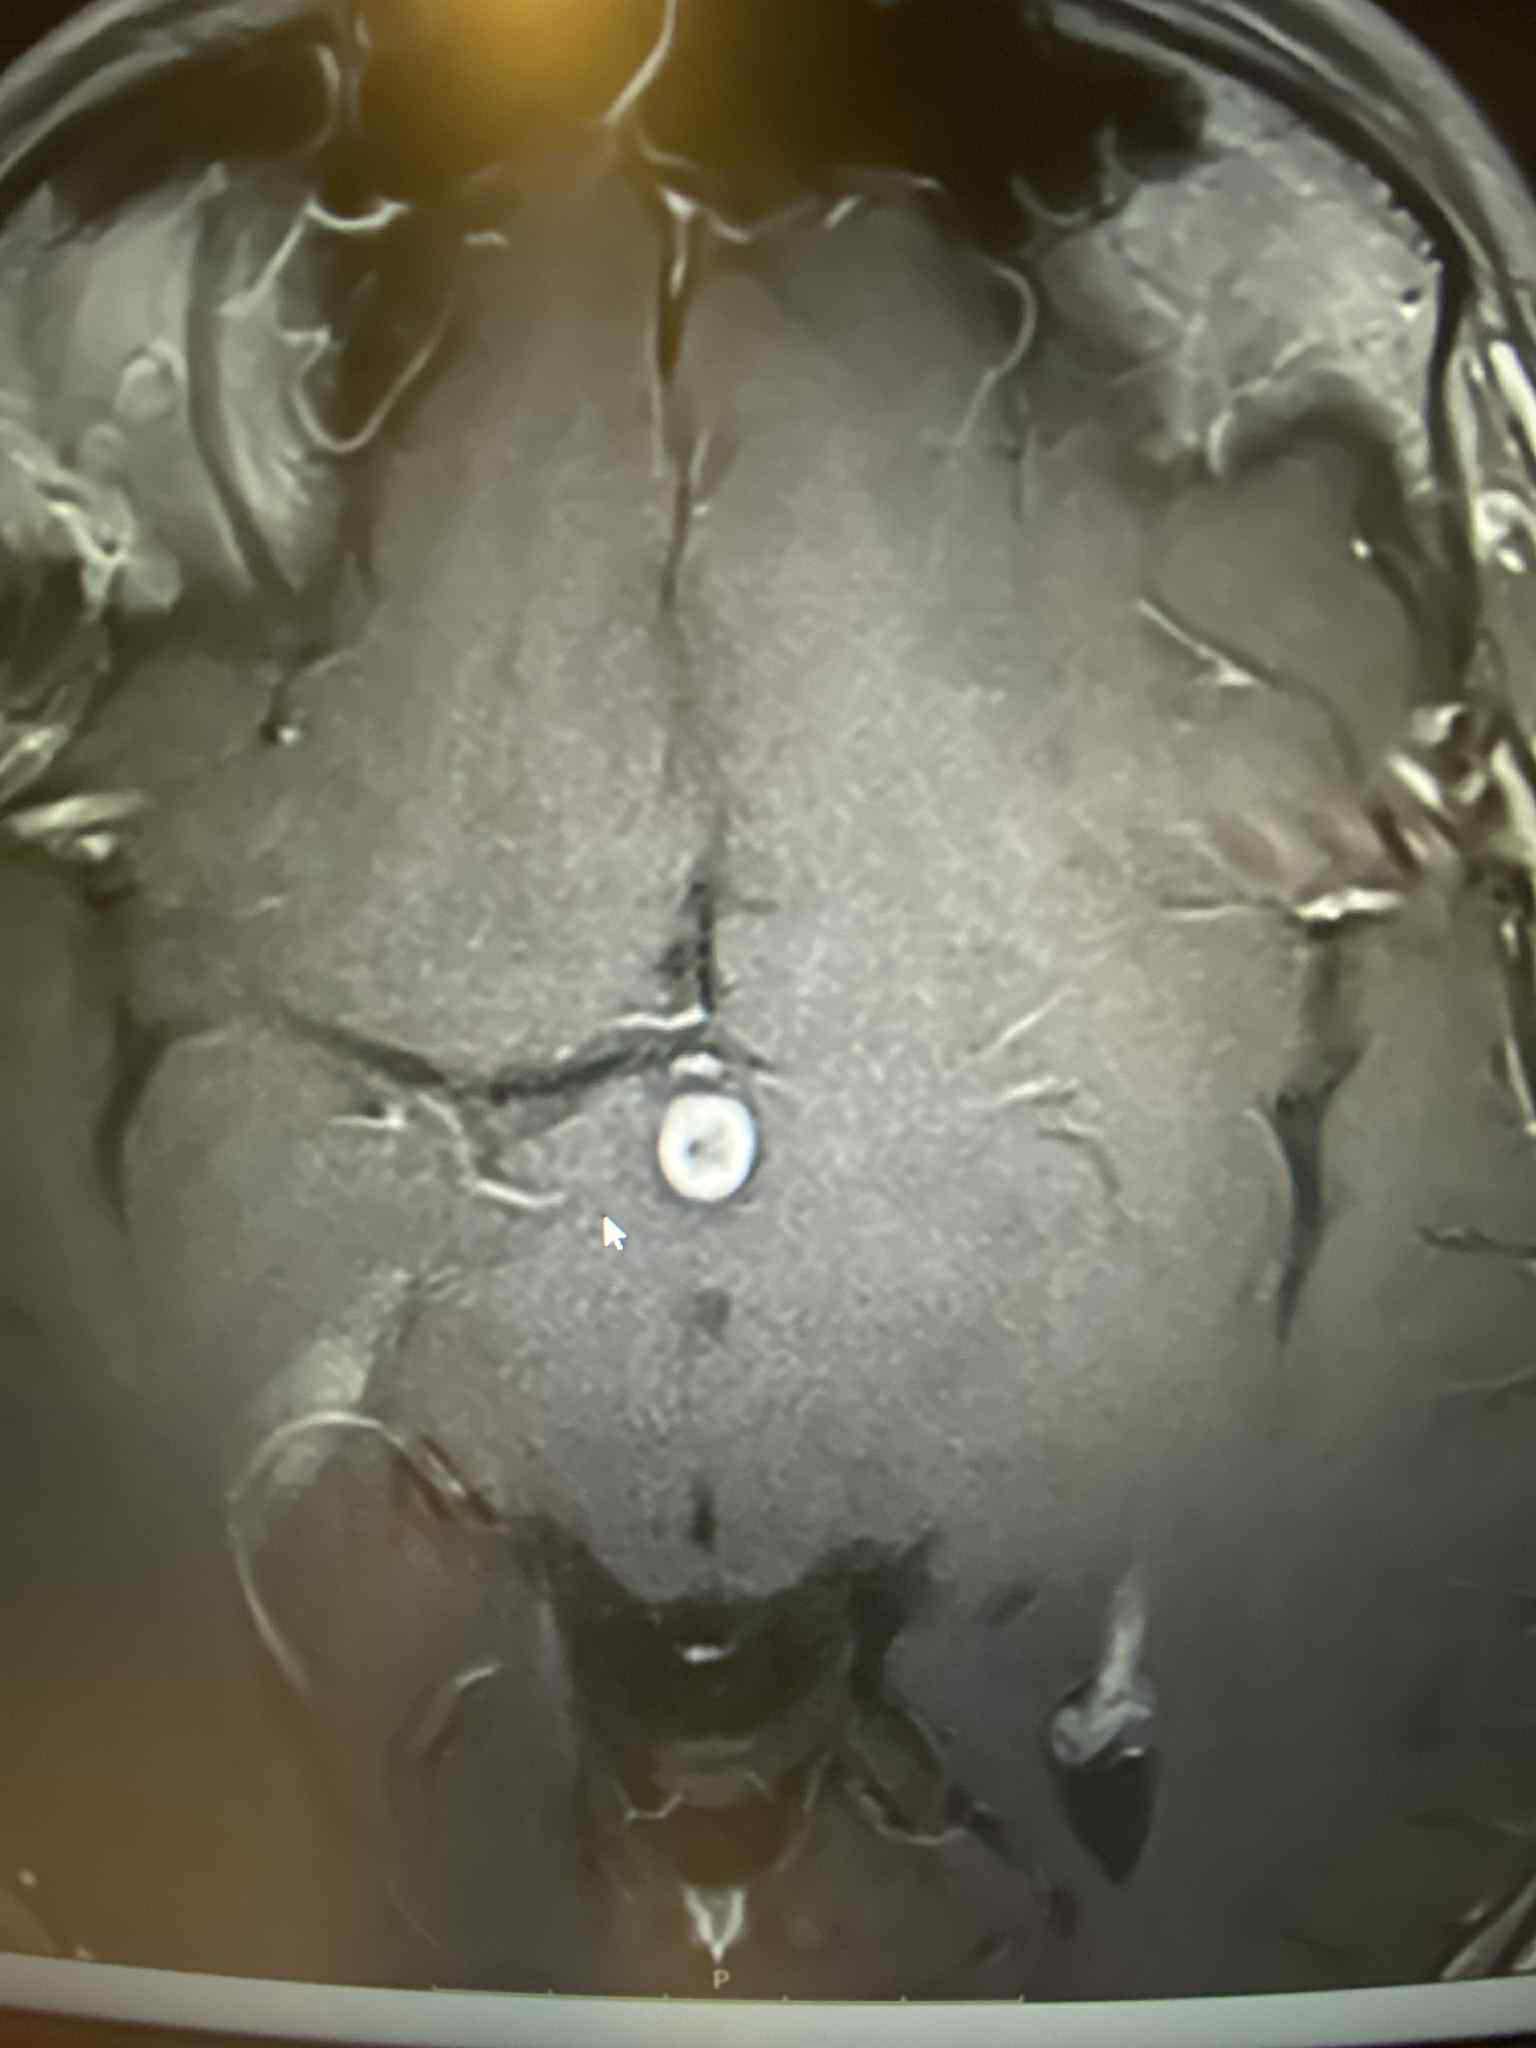

In July he had an MRI done where it showed that he had a tumor on his brain which has grown 4 millimeters as shown by his recent MRI at the start of this month. He has been able to get on an anti-seizure medication but still experiences the nausea, dizziness, headaches and insomnia that the tumor causes. He is at high risk for suffering a stroke due to the tumor pressing up against his hypothalamus.